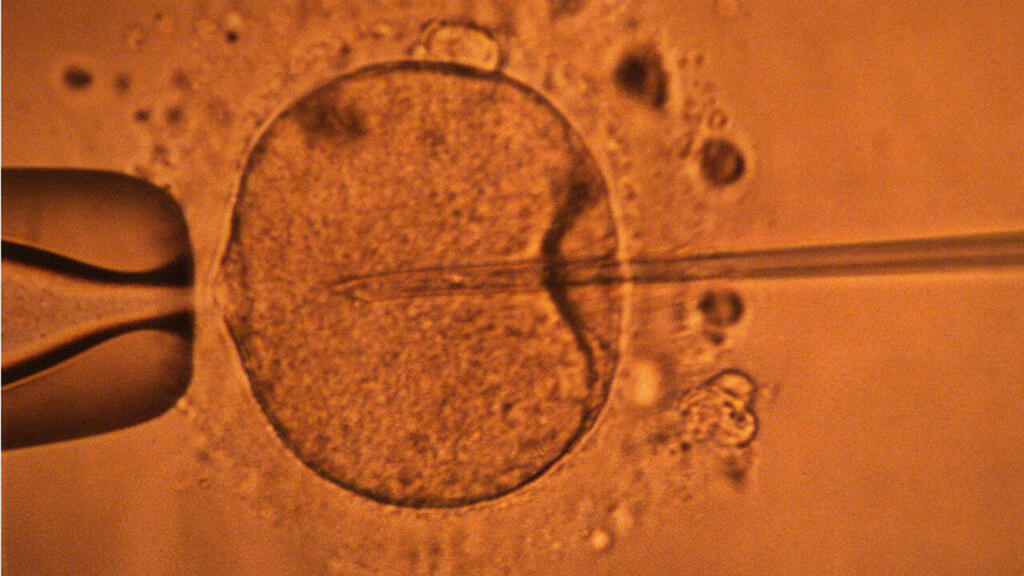

كشفت دراسة جديدة أن عمر الأب يمكن أن يؤثر على صحة الجنين. فكلما تقدم الرجل في السن، زادت فرص ظهور طفرات جينية ضارة في حيواناته المنوية، مما قد يؤثر على فرص الحمل وصحة الطفل.

تعد العوامل الجينية من أهم العوامل التي تؤثر على صحة الجنين. حيث يمكن أن تؤدي الطفرات الجينية إلى ظهور أمراض وراثية أو تشوهات خلقية. وقد وجدت الدراسة أن عمر الأب يمكن أن يلعب دورًا هامًا في زيادة فرص ظهور هذه الطفرات.

كلما تقدم الرجل في السن، زادت فرص تدهور جودة حيواناته المنوية. وهذا قد يؤدي إلى زيادة فرص الحمل بطفل مصاب بمرض وراثي أو تشوه خلقي. وقد وجدت الدراسة أن الرجال الذين تزيد أعمارهم على 40 عامًا يملكون فرصًا أعلى لحدوث طفرات جينية ضارة في حيواناتهم المنوية.